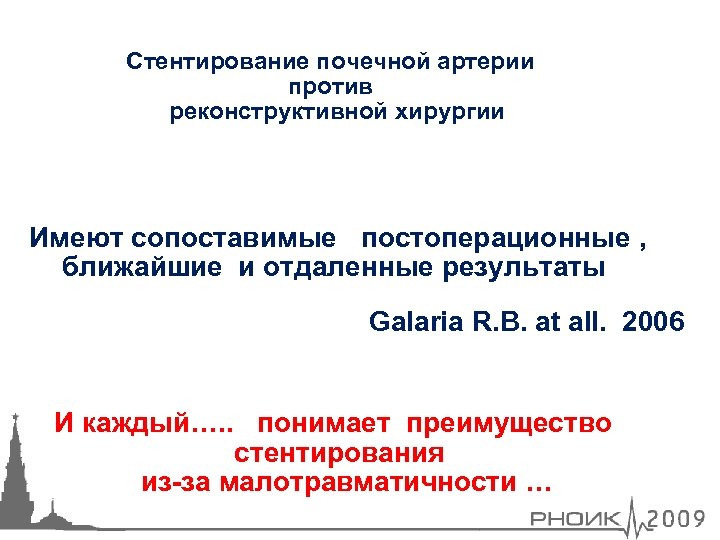

Стентирование почечной артерии против реконструктивной хирургии Имеют сопоставимые постоперационные , ближайшие и отдаленные результаты Galaria R. B. at all. 2006 И каждый…. . понимает преимущество стентирования из-за малотравматичности …

Стентирование почечной артерии против реконструктивной хирургии Имеют сопоставимые постоперационные , ближайшие и отдаленные результаты Galaria R. B. at all. 2006 И каждый…. . понимает преимущество стентирования из-за малотравматичности …